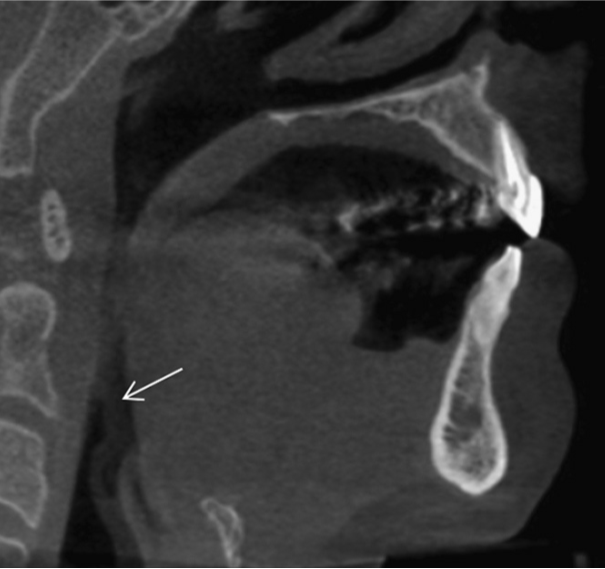

39 / 46

39) Identify the artifact in this CBCT image? (1 mark)